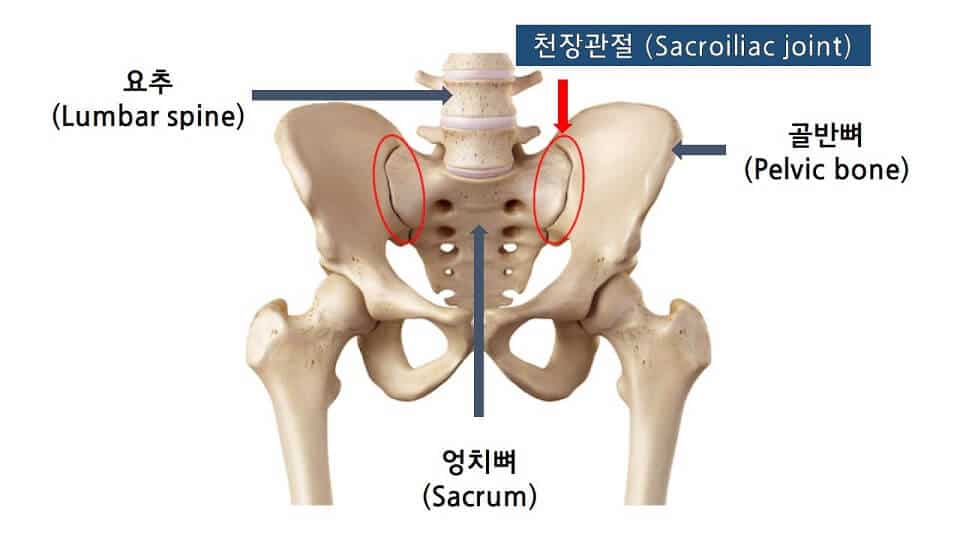

천장관절은 골반의 좌우측에 있는 골반뼈와 천골을 연결하는 관절입니다. 이 관절의 문제는 천골에 통증을 유발할 수 있습니다. 긴 척추를 골반까지 무너뜨려 안정성을 높여주는 관절입니다. 근육과 인대가 단단히 연결되어 있기 때문에 트러블이 잘 생기지 않습니다. 주변 인대가 손상되면 관절이 불안정해져 허리, 엉덩이, 허벅지 주변에 통증을 유발할 수 있다.